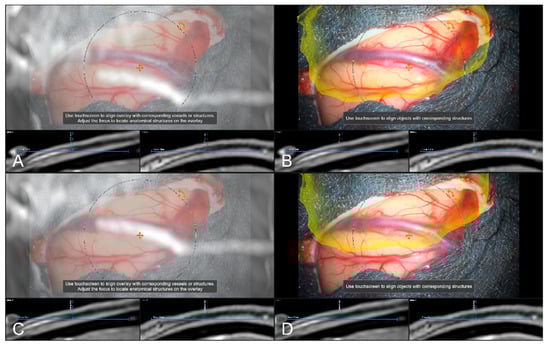

In 242 cases (82.59%), a vascular representation gained by available preoperative CTA, T1-CE, or ToF angiography data was used to evaluate navigation accuracy after dural incision, whereas in the remaining 18 cases (6.14%), no sufficient representation of cortical vascular structures could be obtained due to a lack of sufficient 3D data or poor contrast enhancement. In 43 out of those 242 cases (17.77%), a need to further realign the image data within the recent focus plane (see Figure 7) was seen, whereas in 181 cases (74.79%), navigation accuracy was determined to be sufficient (see Figure 8), partially due to prior evaluation utilizing bony landmarks. In all 43 cases, showing an inaccurate match of image and patient data, these local inaccuracies were successfully compensated for by rigid 2D transformation of the image data by translation on average of 3.00 ± 1.93 mm and a rotation on average of 0.38° ± 1.06°.

Figure 7.

Navigation inaccuracy visualized in the recent focus plane utilizing a MIP of a preoperative T1-CE image showing the translational mismatch of MIP and patient anatomy (A,B) and the match of MIP and patients anatomy in the recent focus plane after manual correction (translation) of the visual misalignment (C,D). (In parallel view of MIP projection and patient anatomy (upper part) and inline views with the recent focus plane (blue line) and the optical axis (dashed blue line) in the bottom part).

Figure 8.

High spatial navigation accuracy seen in the recent focus plane utilizing a MIP of a preoperative T1-CE image (A,C), and patient anatomy enhanced with segmented vascular structures (blue), tumor outlines (yellow) and precentral gyrus (green) (B,D) in two patient cases, showing the different quality of preoperative imaging data (In parallel view of MIP projection and patient anatomy (upper part) and inline views with the recent focus plane (blue line) and the optical axis (dashed blue line) in the bottom part).